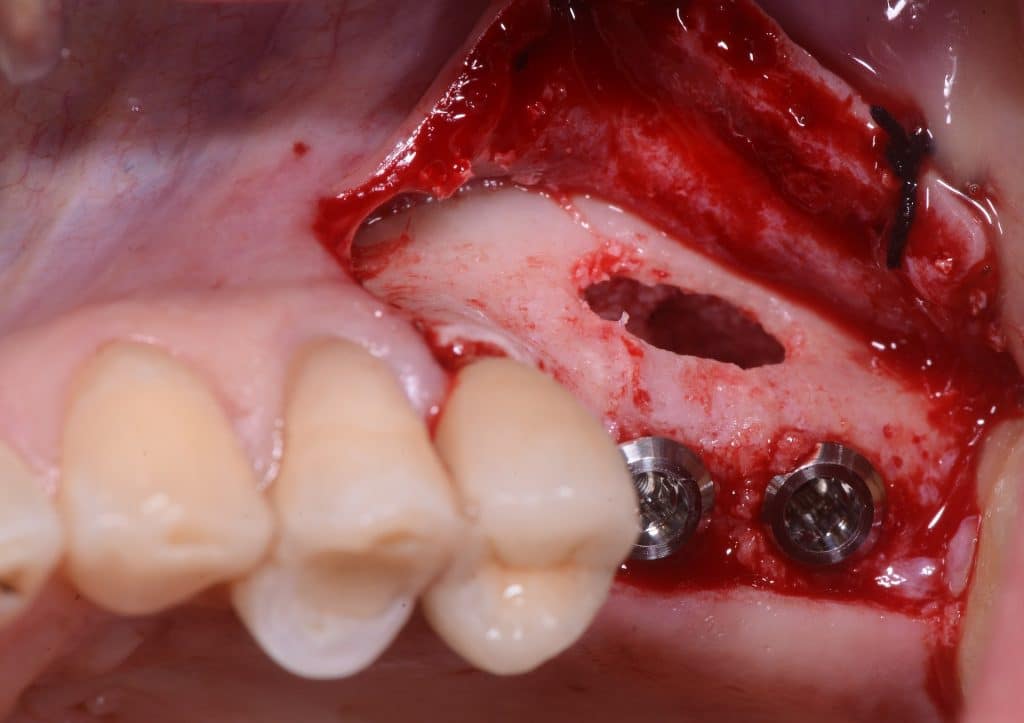

- Two implants are placed drilling the 3 mm of residual crestal bone

- You can see the apexes of the depth indicators inside the maxillary sinus

- Two 8 mm Straumann TLX implants placed

- TLX implants have an excellent primary stability in most cases (as post-extraction cases). But in the case of sinus lift they tend to lose primary stability in the last stages of screwing. Therefore in this case a conical implant is preferable.

- Implants can be seen inside the maxillary sinus through the bone window

- A little more of Bio-oss is inserted

lateral sinus wall, implants view

occlusal view, implants placed